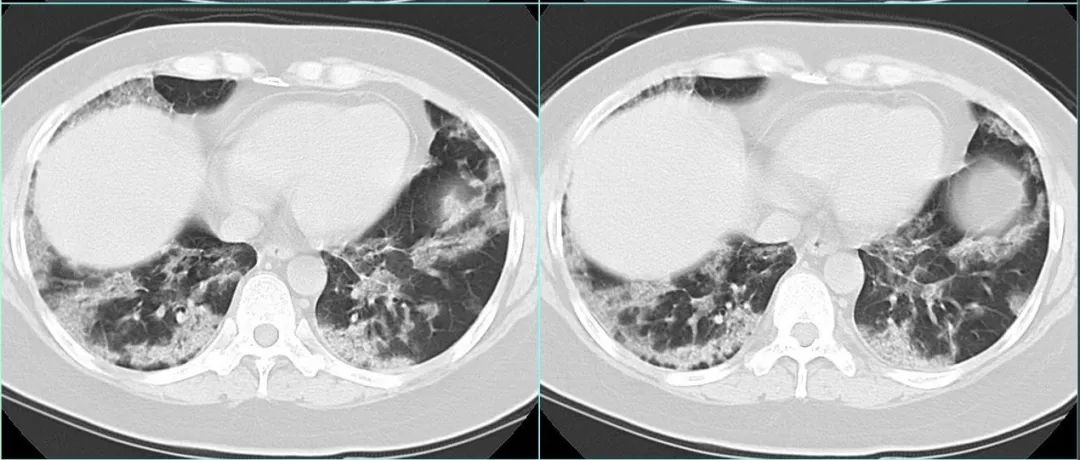

医学影像  yxyx-app  医学影像APP,打造伴随医生快速成长的影像学习社区。与影像园(Xctmr.com)一起提供最全面的影像案例库、基础(解剖、病理、影像诊断)知识、影像技术及考题等,为医生提供最佳的医学影像参考。【所属科室】呼吸科【基本资料】患者,女,41岁【主诉】干咳、气喘10天【现病史】患者于入院前10天受凉后出现咳嗽,干咳无痰,气喘,不能平卧,近4天出现发热,最高体温39℃,食欲减退,食量减少为原来的1/2,无流涕、喷嚏、咽痛,无全身疼痛及关节疼痛。遂来我院就诊,予以头孢米诺静滴7天,左氧氟沙星、地塞米松静滴3天,体温恢复正常,但咳嗽、气喘无明显好转。...